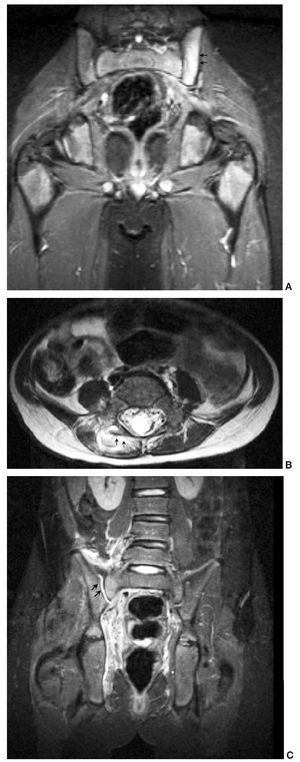

Fig. 4. (A) Afectación osteoarticular. Aumento de señal en el hueso ilíaco izquierdo en secuencia coronal STIR. (B) Afectación osteoarticular. Secuencia axial FSE T2: afectación de la articulación interapofisaria con mínimo derrame articular. (C) Afectación osteoarticular. Secuencia coronal STIR: derrame en la articulación sacroilíaca derecha.

La RM contribuye al diagnóstico diferencial de la piomiositis con otras entidades como la artritis séptica, la osteomielitis, la tromboflebitis y el tumor. Asimismo, la administración de gadolinio identifica la presencia de abscesos, siendo de gran utilidad en el caso de que requieran drenaje percutáneo. Las áreas de piomiositis se manifiestan en una fase inicial como zonas heterogéneas y con elevada señal en las secuencias potenciadas en T2 y STIR. En fases tardías, los abscesos se presentan como áreas de baja señal en T1 y alta señal en T2, que realzan de manera periférica tras la administración de gadolinio (fig. 5), hallazgos que coinciden con la serie presentada por Soler et al21. Cambios en la señal del hueso se vieron en 7 de nuestros casos, mientras que una captación gammagráfica positiva sólo se apreció en 4 casos; esto indica que la RM es altamente sensible para identificar la patología ósea subyacente, aunque es difícil diferenciar si estos cambios en la señal del hueso se deben a la presencia real de osteomielitis o a edema reactivo. En estos casos el citrato de galio-67 y los leucocitos marcados con 111In o 99mTc pueden aumentar la sensibilidad y especificidad de la prueba radioisótopica22,23. El citrato de galio administrado por vía intravenosa se fija a la transferrina y se une a la lactoferrina de los leucocitos, e incluso a las propias bacterias, y se acumula en mayor cantidad en los focos inflamatorios y sépticos.